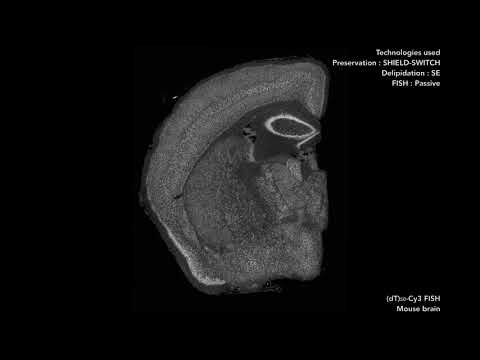

SHIELD is a tissue transformation technology that allows the extraction of multiple biomolecules and multi-scale structures from the same, transparent organ-scale tissue. These unique properties are originated from a polyepoxy chemical. Single polyepoxy has a flexible backbone and multiple epoxide groups that can form intramolecular crosslink with multiple amine groups on the surface of individual biomolecules. Therefore, it can protect tertiary structure of biomolecules and their functions against harsh stressors (e.g., heat, detergents, organic solvents, acidic pH). Polyepoxy can also form crosslinks among multiple endogenous biomolecules to preserve them at their physiological locations and increase the mechanical stability of the tissue-gel.

SHIELD preserves protein fluorescence, nucleic acids, proteins, and their probe binding capability (e.g., antigenicity). SHIELD tissue also safeguards native tissue architecture against tissue clearing and de-labeling treatments. Furthermore, combining with MAP (Magnified Analyses of Proteome; Ku et al., Nature Biotechnology, 2016), SHIELD tissue can be expanded 3~4 folds while preserving all key information (protein fluorescence, proteins, nucleic acids, tissue architecture). This allowed us to reconstruct fluorescence-labeled fine subcellular structures from large tissue volume, such as long-range axon fibers and synaptic boutons.

Further, SHIELD is applicable to various types of tissues. For example, SHIELD can transform long-banked human brain tissue into transparent tissue-gel hybrid. SHIELD can be applied for rapid volumetric phenotyping of fresh tissue biopsies. By combining SHIELD with our Stochastic electrotransport (SE) technique, SHIELD allows preserving, clearing, and immunolabeling fresh intact biopsy (1 mm diameter) only within 4 hours.